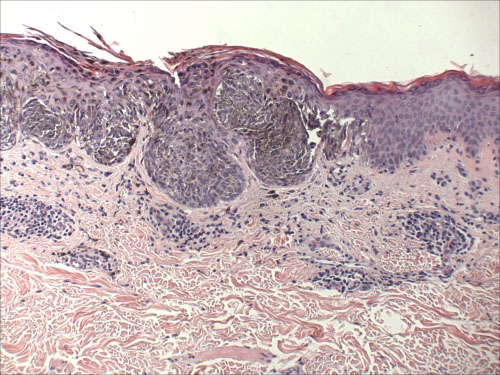

Dysplastic (Clarks) Nevus

Compound melanocytic nevus with architectural disorder and shouldering (S), or extension of the junctional component beyond the dermal nests of melanocytes (D). Rete ridges are irregular and distorted with bridging (B) and eosinophilic fibrosis (arrows). Scattered lymphocytic infiltrate is often present (*).

Dysplastic nevus

Large, oval, multiple c irregular pigmented nests and single melanocytes

- central papule c surrounding macule that fades at border

- junctional part goes at least 3 rete pegs past the intradermal part

- end of retes show club-like hyperplasia

- no deep mits or deep pigment in nests

Low grade - atypical just at the periphery (shoulder region?)

- shoulder goes 0.2 cm beyond the edge of visible lesion

High grade - some parts c lots of cytologic atypia

- high-grade lesions can be treated like melanoma in situ

- high-grade lesions may recur and look atypical, but usually the same

Architecturally Disordered Nevus (ADN)

- aka dysplastic nevus, Clark nevus, atypical nevus

Should specify the degree of atypia (mild, moderate, severe)

- those with a severe degree of atypia are more likely to become melanomas

Histo: >5 cm, melanocytic rests at sides and tips of rete ridges, bridging c melanocytic hyperplasia, lamellar / concentric fibroplasia next to nests, no pagetoid involvement of overlying dermis, little halo change, mild to moderate atypia, macronucleoli in proliferating melanocytes, can have holes in melanocyte expression

- difficult to dx if <0.5 cm

- angulated, hyperchromatic atypical nuclei and bridging c nests and neighboring rete pegs and stromal response

- Shouldering: epidermal component extends beyond dermal

- inc numbers of single melanocytes

Lesion looks more malignant as pt ages and the lesion becomes darker

- may just be arbitrary distinctions between this and melanoma

Assoc w CDKN2A: encodes cyclin-dependent kinase inhibitor 2A, which regulates bwt G1/S by binding cyclin-dependent kinase CDK4

~ chr 9p21